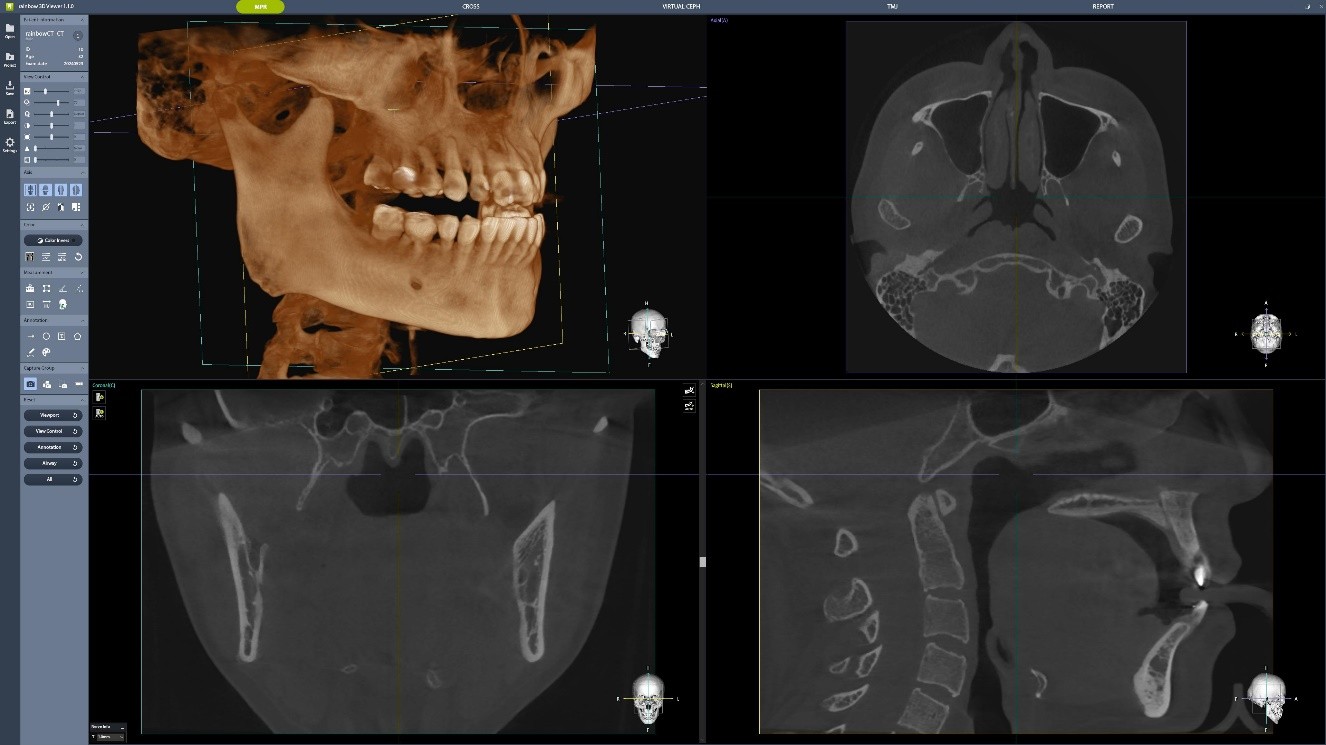

Nerv: Identificarea canalului nervului alveolar inferior se face în doar 15 secunde. Inteligența Artificială Dentium asigură un diagnostic mai precis și de încredere.

Tehnologia MAR Plus – Reducerea Artefactelor Metalice

Dentium MAR (Metal Artifact Reduction) reduce automat artefactele metalice cauzate de implanturi, obturații sau restaurări, asigurând imagini clare și precise. Aceasta contribuie la confirmarea diagnosticului și minimizează riscul de interpretare greșită.